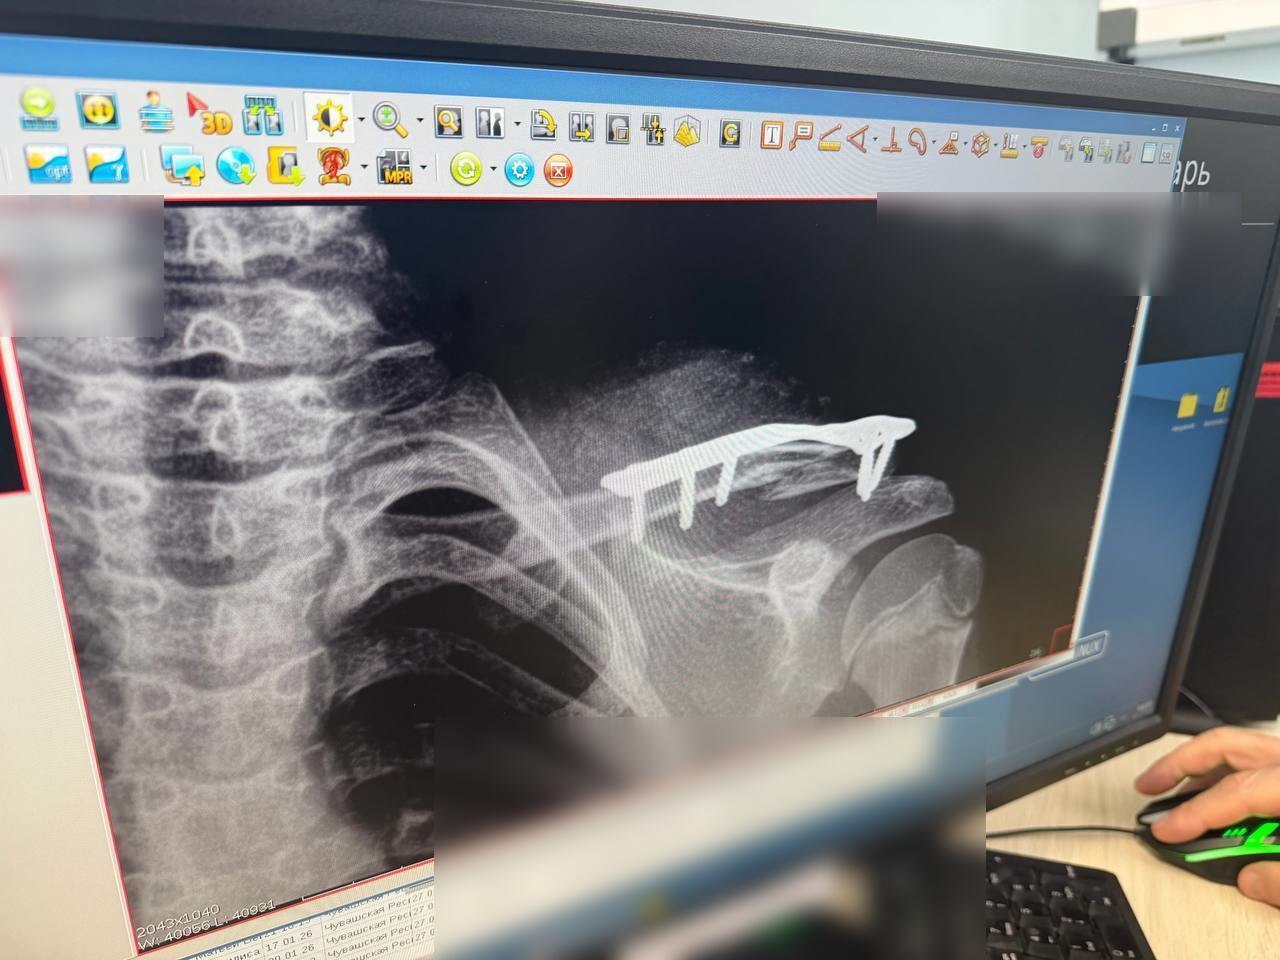

По словам заведующего травматологическим отделением Игоря Ластухина, врачи фиксируют переломы голени, бедра, плечевой кости, компрессионные переломы позвоночника и другие серьёзные повреждения. Основные причины повторяются из случая в случай: катание в неположенных местах, по несколько человек на одной «ватрушке» и отсутствие контроля со стороны взрослых.

Один из тяжёлых случаев произошёл в Новочебоксарске, где 11-летняя девочка каталась в овраге. Ребёнка экстренно доставили в больницу с компрессионным переломом трёх поясничных позвонков. Ей рекомендовано ношение корсета и ограничение физических нагрузок минимум на полгода. Другой 11-летний мальчик получил перелом ключицы после столкновения с другим ребёнком на тюбинге. Потребовалось оперативное вмешательство, впереди — длительное лечение и повторная операция.